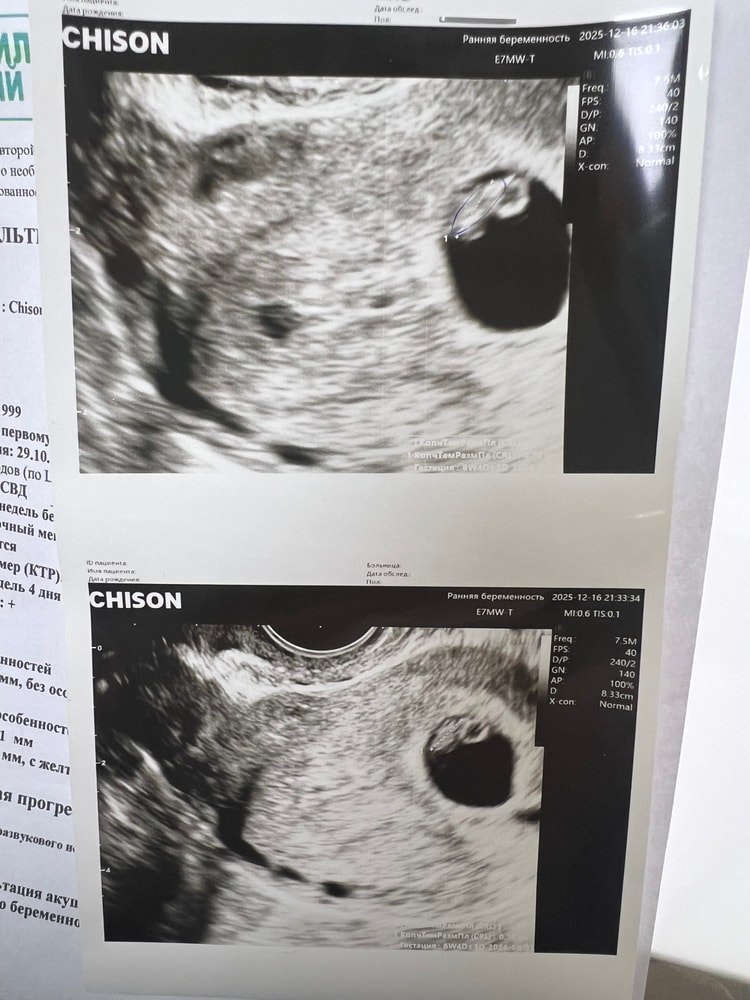

Ктр 7 мм

плодное яйцо 21 мм

желточный мешочек 4 мм

по размерам отстаем на два денечка, в целом не страшно сказали) главное сердцебиение +